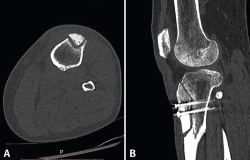

Visto por nosotros a la semana del accidente, presenta un derrame que se evacua y dolor a la palpación del tercio proximal de la tibia con impotencia funcional. La Rx muestra una imagen compatible con fractura metafisodiafisaria proximal de la tibia. Se realiza una TAC (Figura 2) que confirma los hallazgos de la Rx: la fractura afecta a toda la circunferencia, el trazo más distal se encuentra a 37 mm del tornillo distal en la cortical lateral, a 17 mm en la cortical posterior, prácticamente a la altura del tornillo en la cortical medial y sobrepasando levemente el tornillo distal a nivel anterior. Igualmente, se constata una falta de consolidación de la osteotomía de la TTA. Se decide llevar a cabo tratamiento conservador y se inmoviliza con ortesis cruopédica termoplástica, descarga completa con muletas y se inicia magnetoterapia, así como tratamiento con bifosfonatos, calcio y vitamina D.

Figura 2. A y B: la tomografía axial computarizada muestra la fractura metafisodiafisaria no desplazada que afecta a toda la circunferencia y la falta de consolidación de la osteotomía de la tuberosidad tibial anterior.